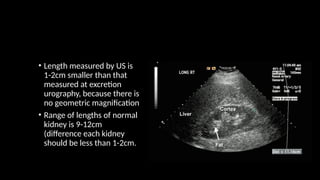

• Length measured by US is

1-2cm smaller than that

measured at excretion

urography, because there is

no geometric magnification

• Range of lengths of normal

kidney is 9-12cm

(difference each kidney

should be less than 1-2cm.